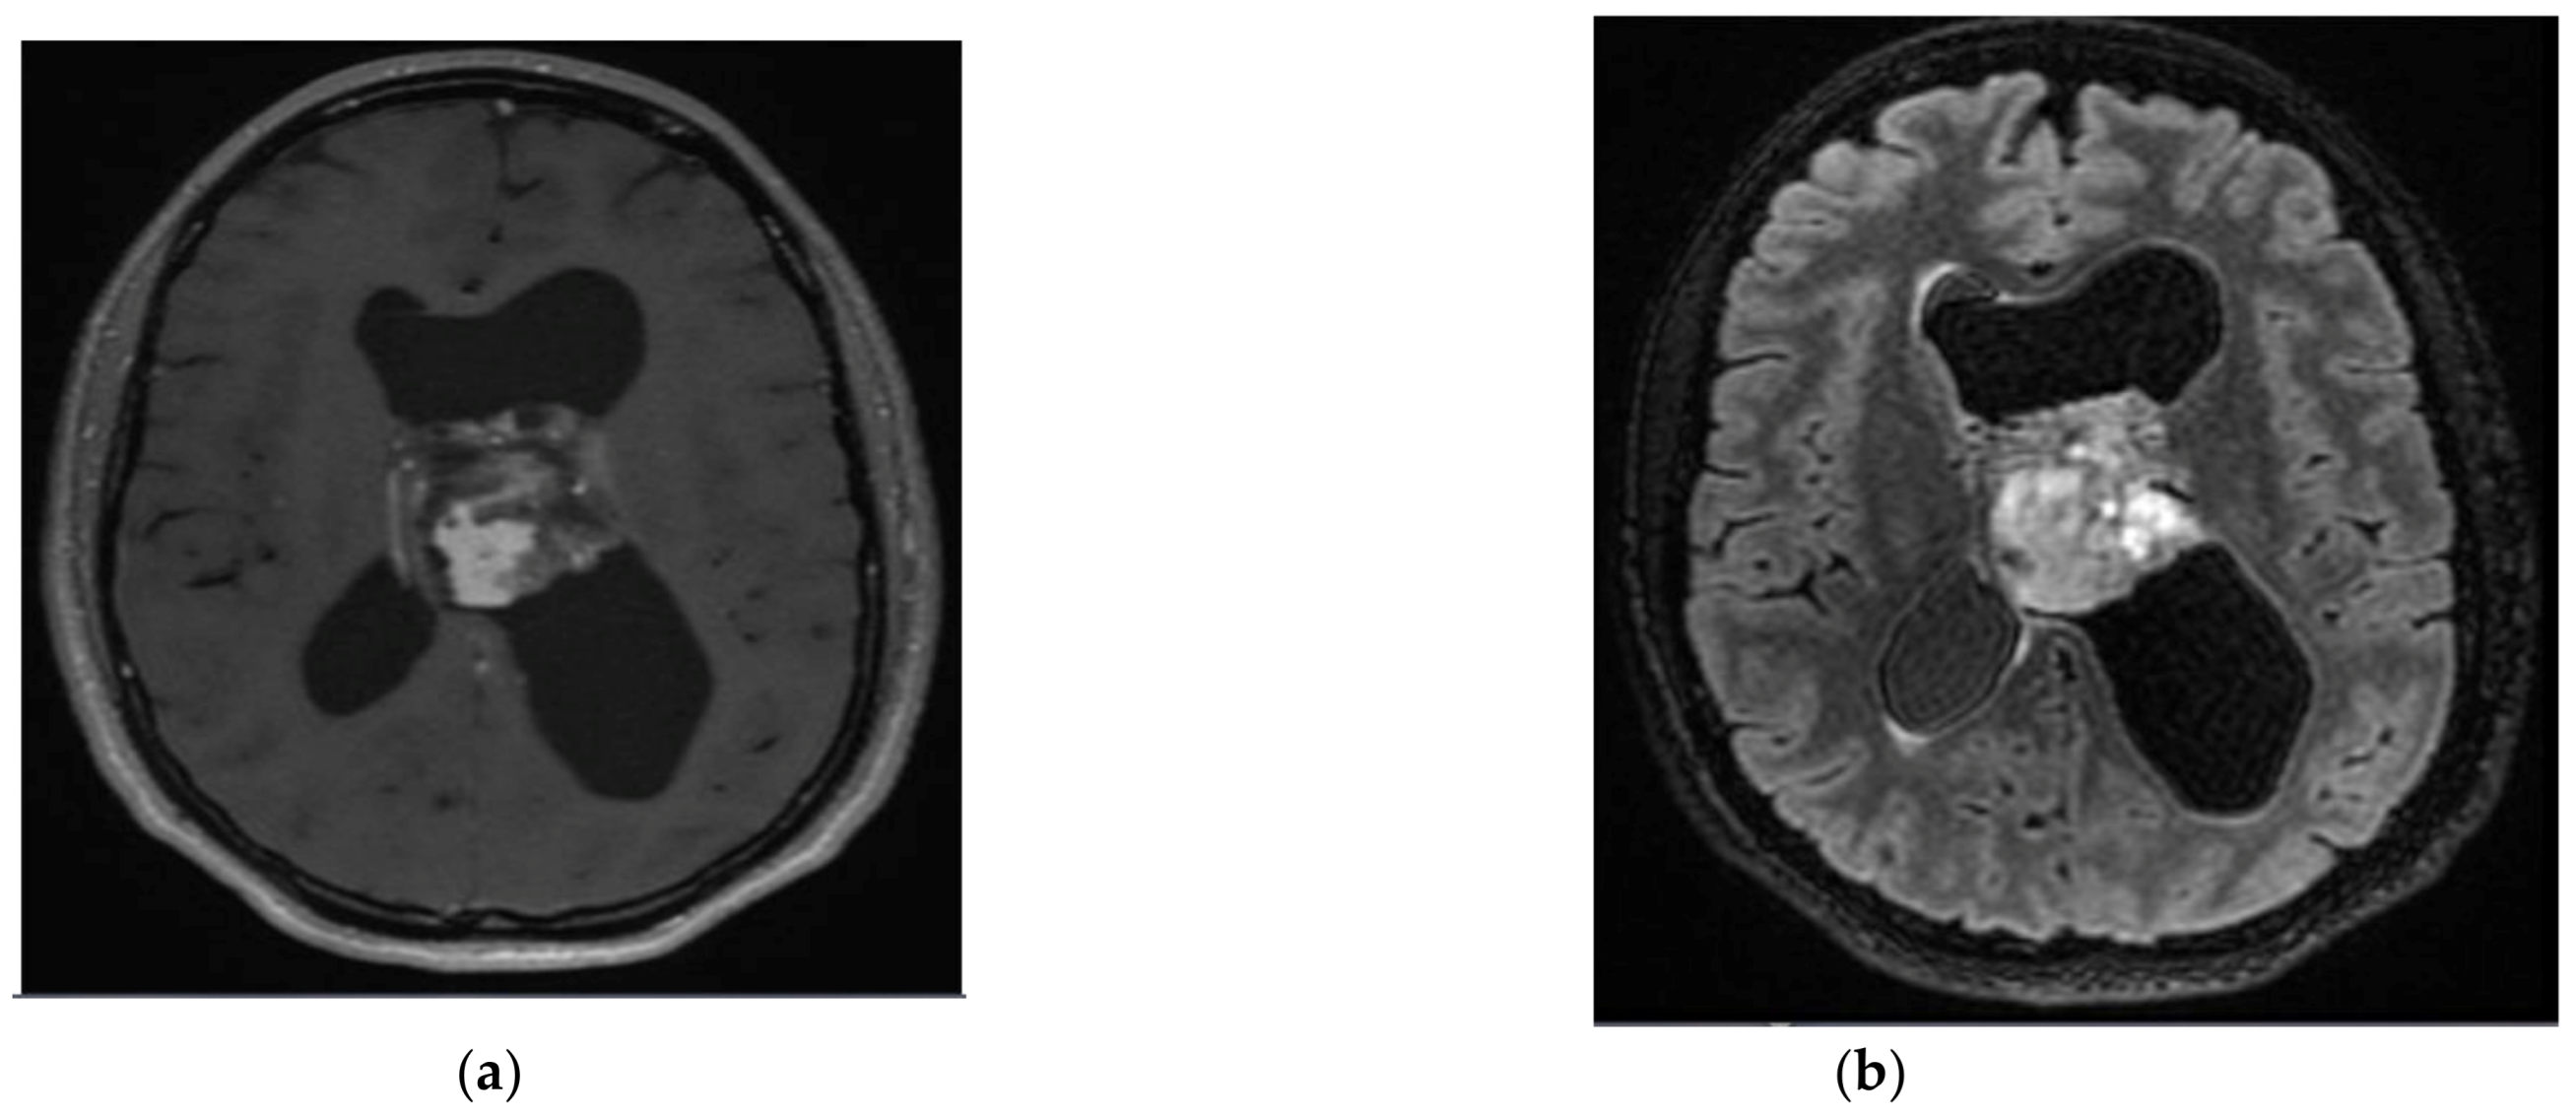

2.2. Central Neurocytoma

- Li, X.; Guo, L.; Sheng, S.; Xu, Y.; Ma, L.; Xiao, X.; Si, Z.; Chen, Y.; Wu, Y. Diagnostic value of six MRI features for central neurocytoma. Eur. Radiol. 2018, 28, 4306–4313. [Google Scholar] [CrossRef]

- Niiro, T.; Tokimura, H.; Hanaya, R.; Hirano, H.; Fukukura, Y.; Sugiyma, K.; Eguchi, K.; Kurisu, K.; Yoshioka, H.; Arita, K. MRI findings in patients with central neurocytomas with special reference to differential diagnosis from other ventricular tumours near the foramen of Monro. J. Clin. Neurosci. 2012, 19, 681–686. [Google Scholar] [CrossRef]